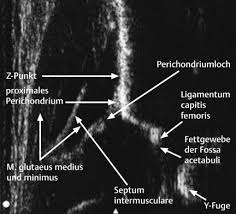

Η εξέταση πραγματοποιείται με τη μέθοδο Graf, η οποία αποτελεί διεθνές πρότυπο.

- Εμπειρία στη μέθοδο Graf (ο κ.Νικόλαος Καλύβας είχε την τύχη και την τιμή να εκπαιδευτεί στον Υπερηχογραφικό έλεγχο των νεογνικών ισχίων από τον ίδιο τον Reinhard Graf )